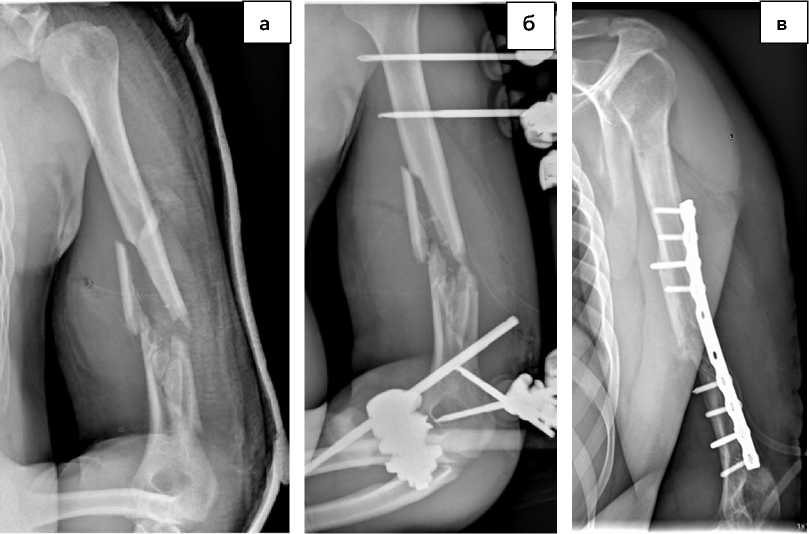

Рисунок 3. Рентгенограмма области плеча при поступлении без фиксации многооскольчатого фрагментарного перелома средней и дистальных третей диафиза плечевой кости со смещением (а), после выполнения остеосинтеза стержневым аппаратом внешней фиксации (б), после выполнения остеосинтеза накостной пластиной на 8-ми винтах, с минимальным смещением в стадии консолидации (в) Figure 3. Radiograph of the shoulder area upon admission without fixation of a multi-fragmentary fragmentary fracture of the middle and distal thirds of the humerus diaphysis with displacement (a), after osteosynthesis with an external fixation rod apparatus (б), after osteosynthesis with an 8-screw bone plate, with minimal displacement in the consolidation stage (в)

Рисунок 4. Рентгенограммы использования методики последовательного остеосинтеза многооскольчатого перелома верхней трети диафиза левой плечевой кости, а – выполнен стержневой остеосинтез, б – выполнен остеосинтез интрамедуллярным винтом

В большинстве случаев на этапе оказания специализированной помощи использовали последовательное выполнение различных видов остеосинтеза (рис. 3, 4) с сопровождением каждого метода фиксации рентгенографическим исследованием.